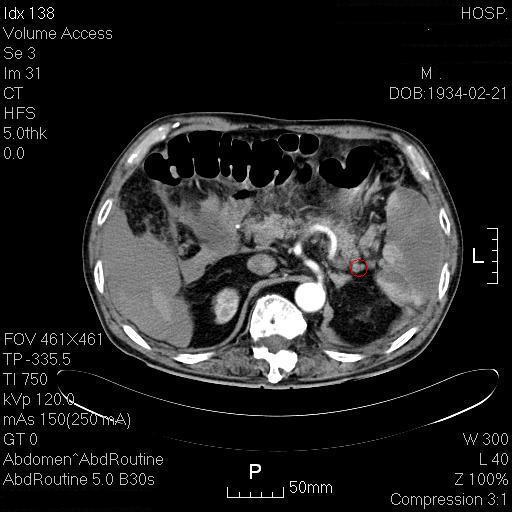

(红圈标注为栓塞的脾动脉)

肝周有积血!脾脏符合梗塞后改变

患者有房颤,未抗凝,脾动脉栓塞致脾梗死,脾脏自发破裂出血。经过输液输血治疗,患者病情转平稳,沟通后,考虑患者高龄,决定不行脾切除。保守治疗半月,无继续出血,患者出院。